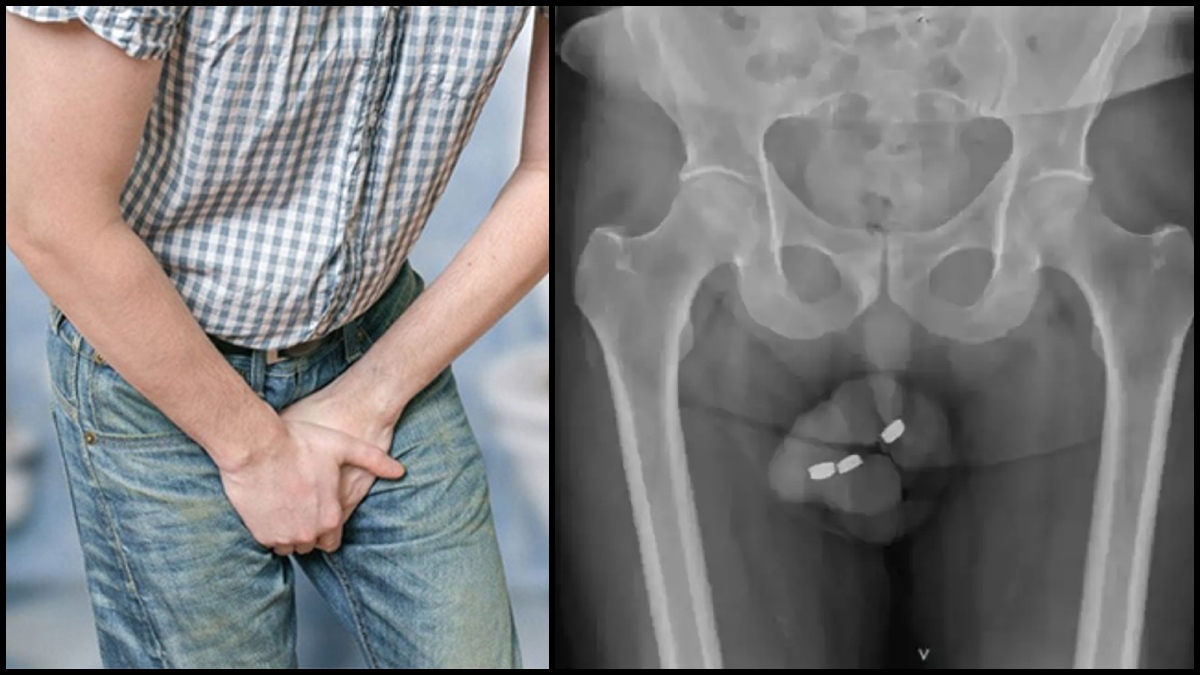

மருத்துவமனையில் மருத்துவர்கள் அவரை பரிசோதனை செய்ததில், பேட்டரியானது சிறுநீர் குழாய் நெப்ரோசிஸ் பகுதியில் சிக்கியுள்ளது. இப்படியொரு வழக்கு இதுவரை உலகில் பதிவானது இல்லை. இது தான் முதல் முறையாகும். அதுவும் இந்த முதியவர் பேட்டரியை ஆணுறுப்பில் சிக்கிய 24 மணிநேரத்திற்கு பின் மருத்துவமனைக்கு வந்துள்ளார். அதுவும் அவருக்கு ஆணுறுப்பில் கடுமையான வலி, சிறுநீர் கழிப்பதில் சிரமம் என பல பிரச்சனைகள் ஏற்பட்டுள்ளது.

ஆனால் அந்த பேட்டரியில் உள்ள அமிலம் கசிந்து, அவருக்க நெக்ரோசிஸை ஏற்படுத்திவிட்டது. நெக்ரோசிஸ் என்பது திசுக்களை இறக்கச் செய்யும் நிலை. நிபுணர்களின் கூற்றுப்படி, நெக்ரோசிஸை சரிசெய்ய முடியாது மற்றும் இது உயிரைப் பறிக்கும் அளவில் ஆபத்தானது.

மருத்துவர்கள் அறுவை சிகிச்சை செய்து அந்த பேட்டரியை மற்றும் சுற்றியிருந்த இறந்த பகுதியையும் அகற்றிவிட நினைத்தனர். ஆனால் அவ்வளவு எளிதில் பேட்டரியை அகற்ற முடியவில்லை. சற்று சிரமப்பட்டனர். பேட்டரியை அகற்ற அறுவை சிகிச்சை மேற்கொண்ட போது, பேட்டரியில் இருந்து கருப்பு நிற திரவம் கசிந்து, ஆணுப்பை மோசமா பாதித்துள்ளது உடனே மருத்துவர்கள் அந்த முதியவரின் ஆணுறுப்பின் பெரும் பகுதியை அகற்ற வேண்டிய சூழல் ஏற்பட்டது.

இந்த திரவ கசிவால் பாதிக்கப்பட்ட பகுதிக்கு சிகிச்சையை முழுமையாக முடிக்க 6 மாதங்கள் வரை ஆகும். அதே சமயம் இந்த முதியவரின் ஆணுறுப்பு மோசமாக பாதித்திருப்பதால், அதை சீரமைக்க முடியாது என மருத்துவர்கள் கூறியுள்ளனர். தற்போது அந்த முதியவரால் எந்த ஒரு சுகத்தையும் அனுபவிக்க முடியாத நிலையில் உள்ளார்.